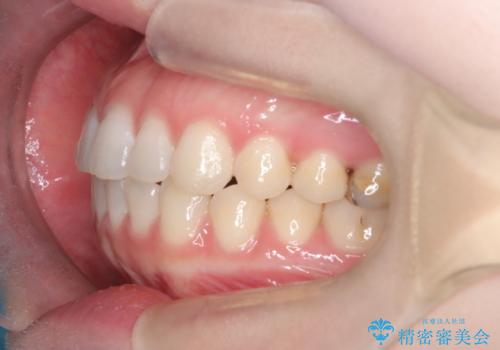

今回のワイヤー矯正治療では、抜歯せずに歯を並べるスペースを作るため、特殊な小さなインプラントであるアンカースクリュー(TAD)を一時的に使用しました。このアンカースクリューを固定源として、奥歯(臼歯部)全体を後方へ遠心移動させました。従来の矯正では難しかったこの奥歯の移動を確実に行うことで、前歯の八重歯を適切な位置に並べるスペースを確保。治療の結果、抜歯することなく右上の八重歯と叢生が解消され、機能的にも審美的にも整った美しい歯並びを獲得していただけました。